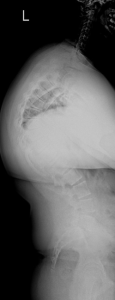

Skoliose

Unter Skoliose versteht man eine dauerhafte Seitverbiegung und Rotation der Wirbelsäule mit gleichzeitiger Verdrehung der Wirbelkörper. Nach ihrer Herkunft lassen sich verschiedene Formen unterscheiden (idiopathisch, kongenital, neuromuskulär, adult), die sich hinsichtlich des Erkrankungsalters, der Ausprägung, des Fortschreitens der Erkrankung und der möglichen Behandlungsverfahren unterscheiden.